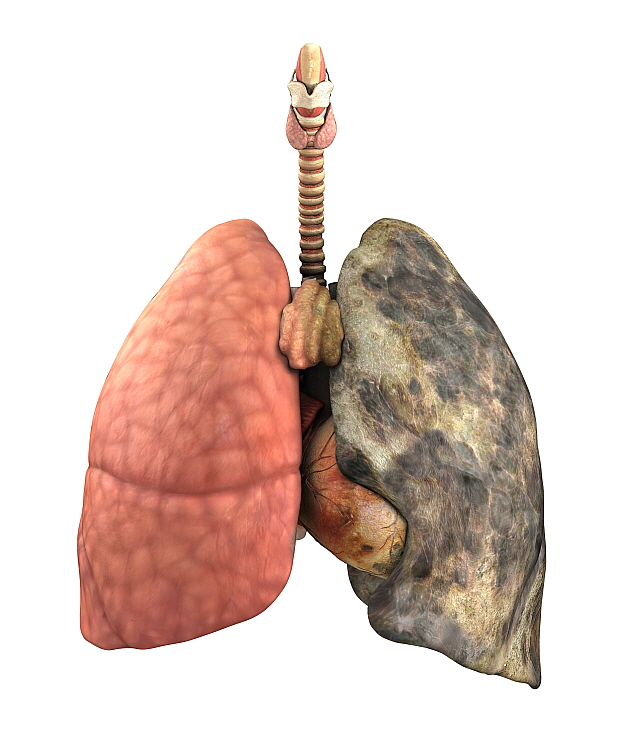

둘째, 환경적 요인이 '폐암'으로 이어질 수 있습니다. 일상 생활에서 흡입되는 발암 물질은 폐암을 유발할 수 있습니다. 즉, 대기오염 가스 중의 발암물질을 흡입하거나 흡연을 통한 발암물질을 직간접적으로 흡입함으로써 폐암이 발생할 수 있습니다. 흡연은 폐에 매우 치명적이어서 흡연은 폐암의 가장 큰 원인이며, 비흡연자도 간접흡연으로 폐암에 걸릴 수 있습니다.

흡연자가 주변에 있으면 비흡연자도 영향을 받는다는 연구 결과가 있습니다. 폐암은 다른 많은 환경적 요인으로 인해 다양한 원인이 있습니다. 또한 폐암은 주로 노인에게 영향을 미치며 40세 미만보다 70세 이상 인구가 더 많습니다. 따라서 나이가 들어감에 따라 정기적인 건강 검진이 필수적입니다.